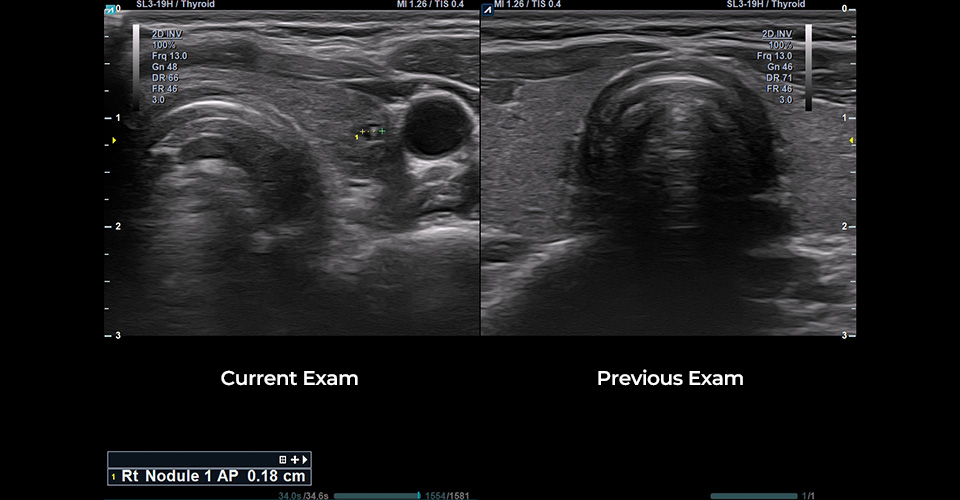

SL3-19H

X+ Crystal Signature™ linear transducer(3~19MHz)

Application:

MSK, Vascular, Small Parts, Breast, TCD, Abdomen, Pediatric, Gynecology, Obstetrics, EM